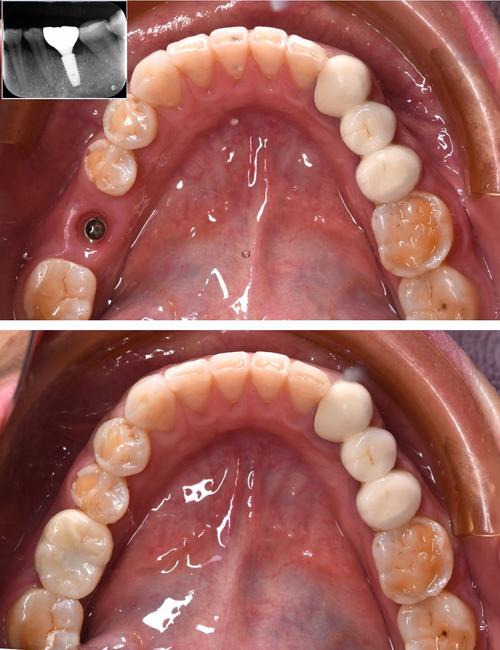

种植牙是通过外科手术将人工种植体植入牙槽骨,作为牙根支持牙冠,属于牙齿修复范畴,其疼痛感受主要来自手术创伤、术后恢复及骨整合期,具体可分为以下几个阶段:

戴牙冠阶段:短暂不适

骨整合完成后,安装基台和牙冠时需切开牙龈(若埋入式种植),可能再次出现切口疼痛,但程度轻、持续时间短(1-3天),牙冠戴入后,若咬合过高,可能出现咬合痛,需医生调磨后缓解。